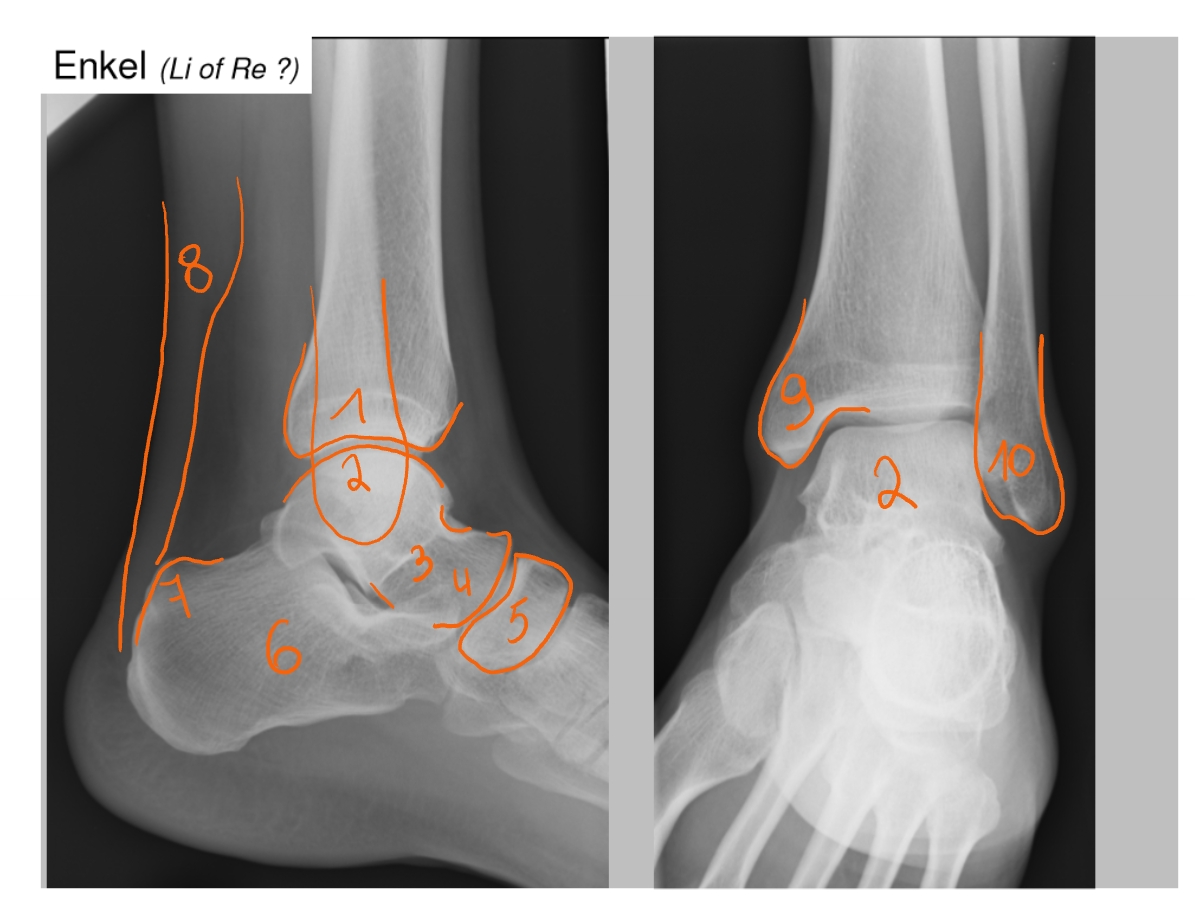

trochlea tibiae

talus

collum tali

caput tali

os naviculare

calcaneus

tuber calcanei

Achillespees → van m. triceps surae

malleolus medialis

malleolus lateralis

→ linker enkel

tibia

talus

calcaneus

Achillespees

gewrichtslijn van Chopart

os naviculare

os cuboideum

ligamentum talo-fibulare anterius

wordt uigerokken/ gescheurd bij een verstuikte voet (als je je voet omslaat)

Achillespees

talus

fibula

os cuneiforme mediale

os cuboideum

os cuneiforme laterale

→ 1e foto: anteroposterieure foto (om de mediale cuneiforme te zien)

→ 2e foto: schuine foto (om de intermediale en laterale cuneiforme te zien)